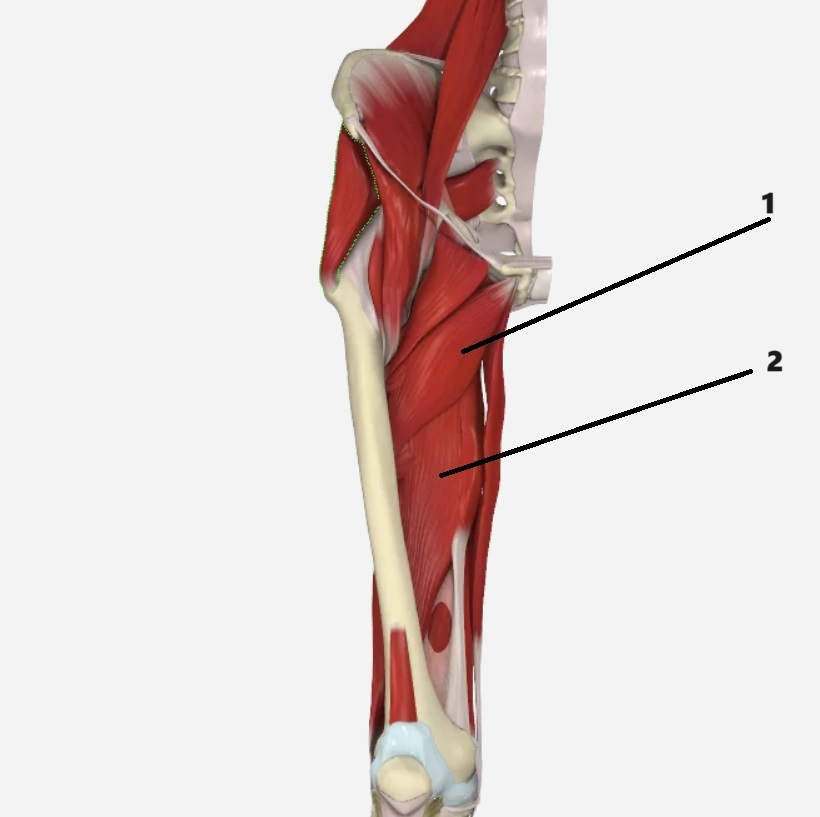

1

adductor brevis

2

adductor magnus

adductor longus